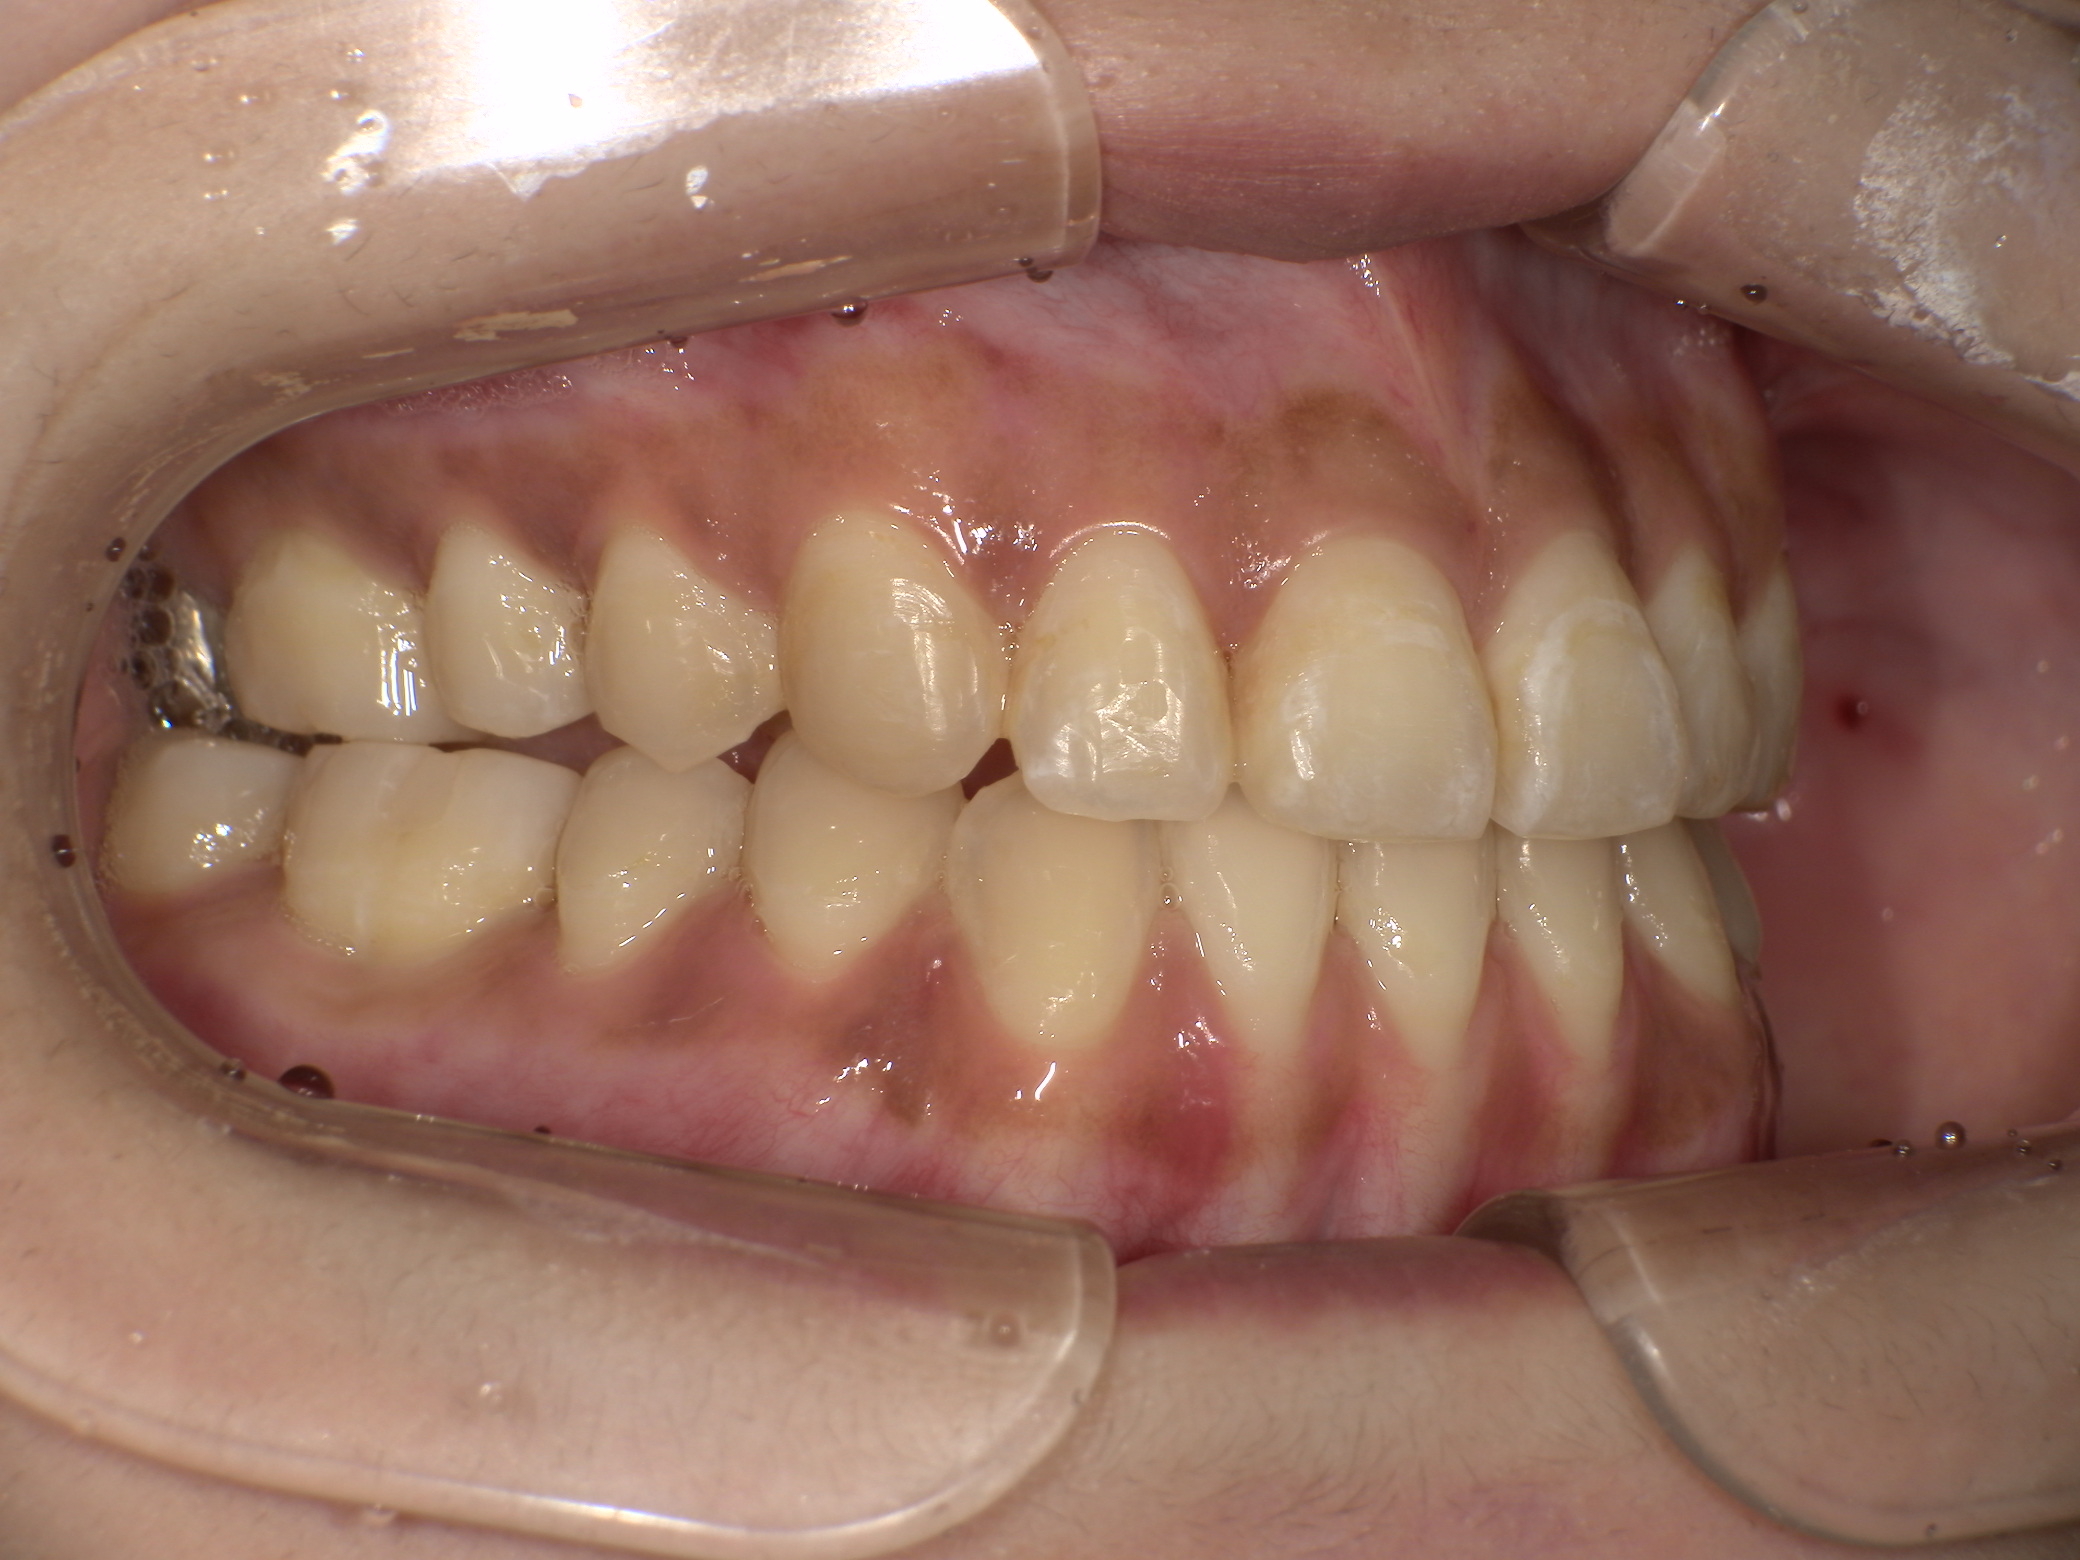

【矯正前】

【主訴】小学生の時途中まで矯正治療をしていたが、最近になって前歯で物が噛めない、噛み合わせの悪さを治したいと大学病院を受診したが、重度の開咬(オープンバイト)のため外科手術が必要と言われた。手術無しで出来る範囲内で治療したい。とのことで当院を受診された20代の女性。

【治療方法】新素材ゴムメタルを使用したGEAW(ギア)システム用い、外科手術も小臼歯抜歯しないで治療を行いました。

【治療期間】1年9か月